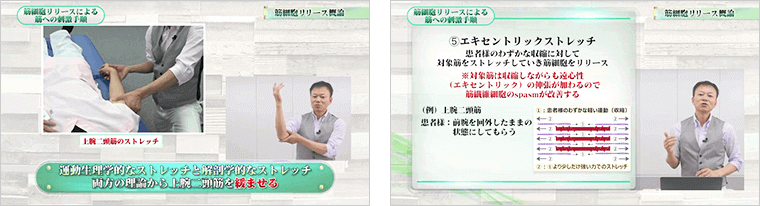

筋繊維細胞が絡まり合って、一切伸び縮みできなくなった状態のことをスパズムと言います。スパズムを放置すると、炎症や可動域制限、圧痛などの機能障害を引き起こします。

長時間に渡る施術をしても痛みや凝りが残ってしまう場合、このスパズムを取り切れていない可能性が高いです。

DISC4でお伝えする筋細胞リリースは、運動生理学と解剖生理学に基づいて、誰でも簡単にスパズムを取り除けるようにノウハウを体系化してまとめてあります。

筋細胞リリースをマスターすれば、筋肉の深層部に残ったしつこいコリや痛み、

癒着さえも一発で解消できるようになります。

- 治療効果を2倍、3倍とUPさせる!軽い圧を5回かけるだけで、緊張してこり固まった筋肉をユルンユルンにする“Ib抑制”とは?

緊張してこり固まった筋肉…あなたはどのように対処していますか?もし、筋肉を緩めることなく治療を始めているのであれば要注意。なぜなら、筋肉がこり固まった状態では、治療効果が弱まってしまうからです。ここでお伝えする“Ib抑制”を取り入れれば、あなたの治療効果を2倍も3倍も引き上げることが可能になります。